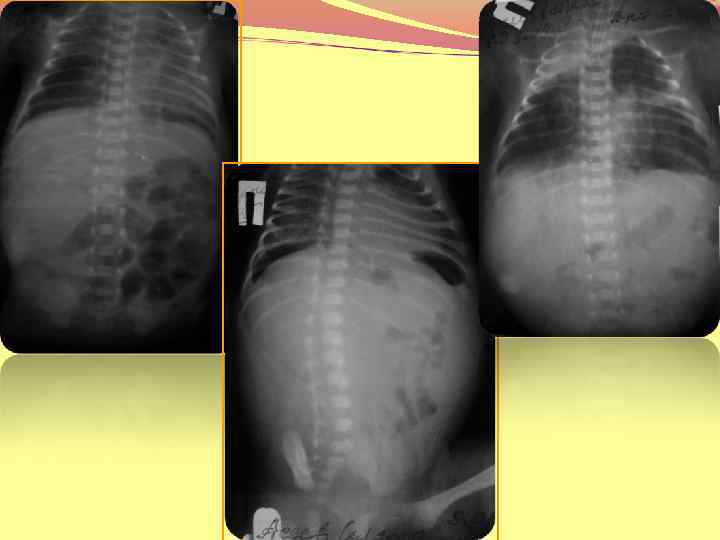

Эмфизема легких диффузная